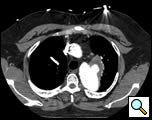

The patient is a 33 year old male with a history of juxtaductal coarctation who underwent a repair early in infancy. The patient had a recurrence of the coarctation and underwent a second open repair and left diaphragm plication at 2 years of age. He was lost to follow-up until recently when he presented to an emergency room with a several week history of hemoptysis and left back pain. The patient’s physical exam was remarkable only for a well-healed left thoracotomy incision. The patient was afebrile with equal blood pressures in all 4 extremities. The patient’s white count was normal. A CT scan of the chest demonstrated a saccular aneurysm of the proximal descending thoracic aorta measuring approximately 6cm in diameter (Figure 1). The patient was transferred to the Oregon Health and Sciences University for further management.